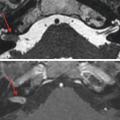

Toute surdité unilatérale ou asymétrique impose une IRM pour détecter un schwannome vestibulaire, tumeur bénigne développée aux dépens du nerf vestibulaire inférieur (fig. 4) ou d’autres processus expansifs de l’angle ponto-cérébelleux.

IRM cérébrale avec étude spécifique des conduits auditifs internes (CAI) et des oreilles internes. Analyse fine des paquets nerveux acoustico-faciaux et des oreilles internes. Séquences sans et avec injection de gadolinium notamment pour mettre en évidence un schwannome (prise de contraste nodulaire centrée sur le nerf vestibulo-cochléaire) ou encore une labyrinthite.